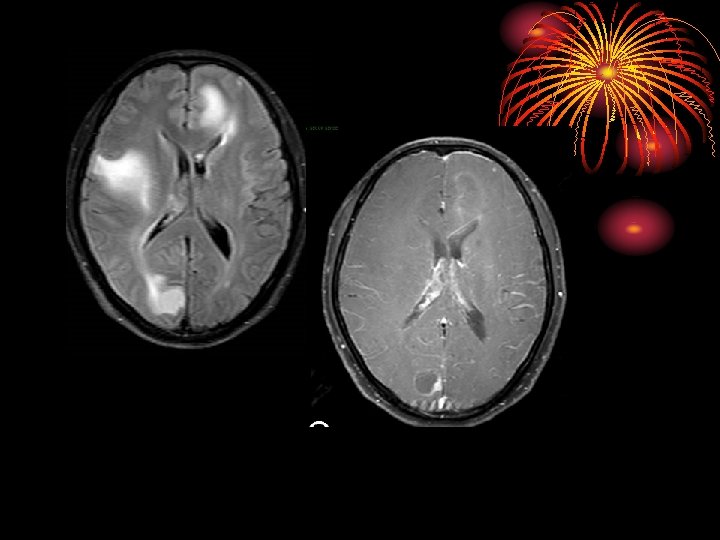

激素治 疗后好 转 2 months after corticosteroid therapy 50 -year-old man presenting with slurred speech and